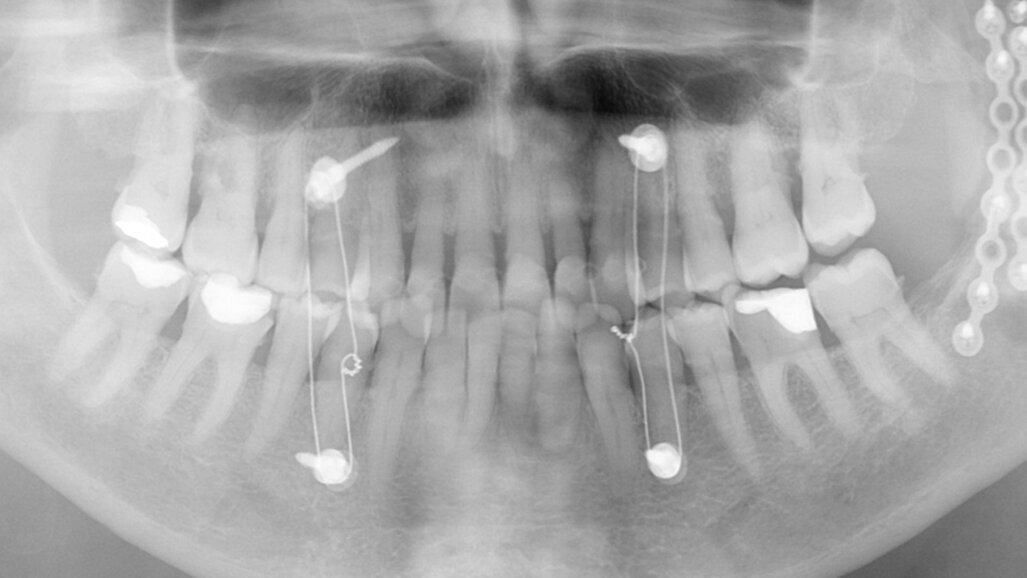

Fig. 13: Final radiograph used to check for excess cement around the bridge.

One week later, the extraction socket, which was still healing, was modelled for the ovoid pontic using an electrotome loop. The second premolar and molar were prepared as abutment teeth for a bridge. The bridge was then designed (Figs. 4–6) and milled from KATANA Zirconia Block for Bridge in Shade A3.5 and individualised with CERABIEN ZR FC Paste Stain (both Kuraray Noritake Dental; Figs. 7–10). A further week later, the bridge was luted with the self-adhesive resin cement PANAVIA SA Cement Universal after sandblasting (Figs. 11–13).